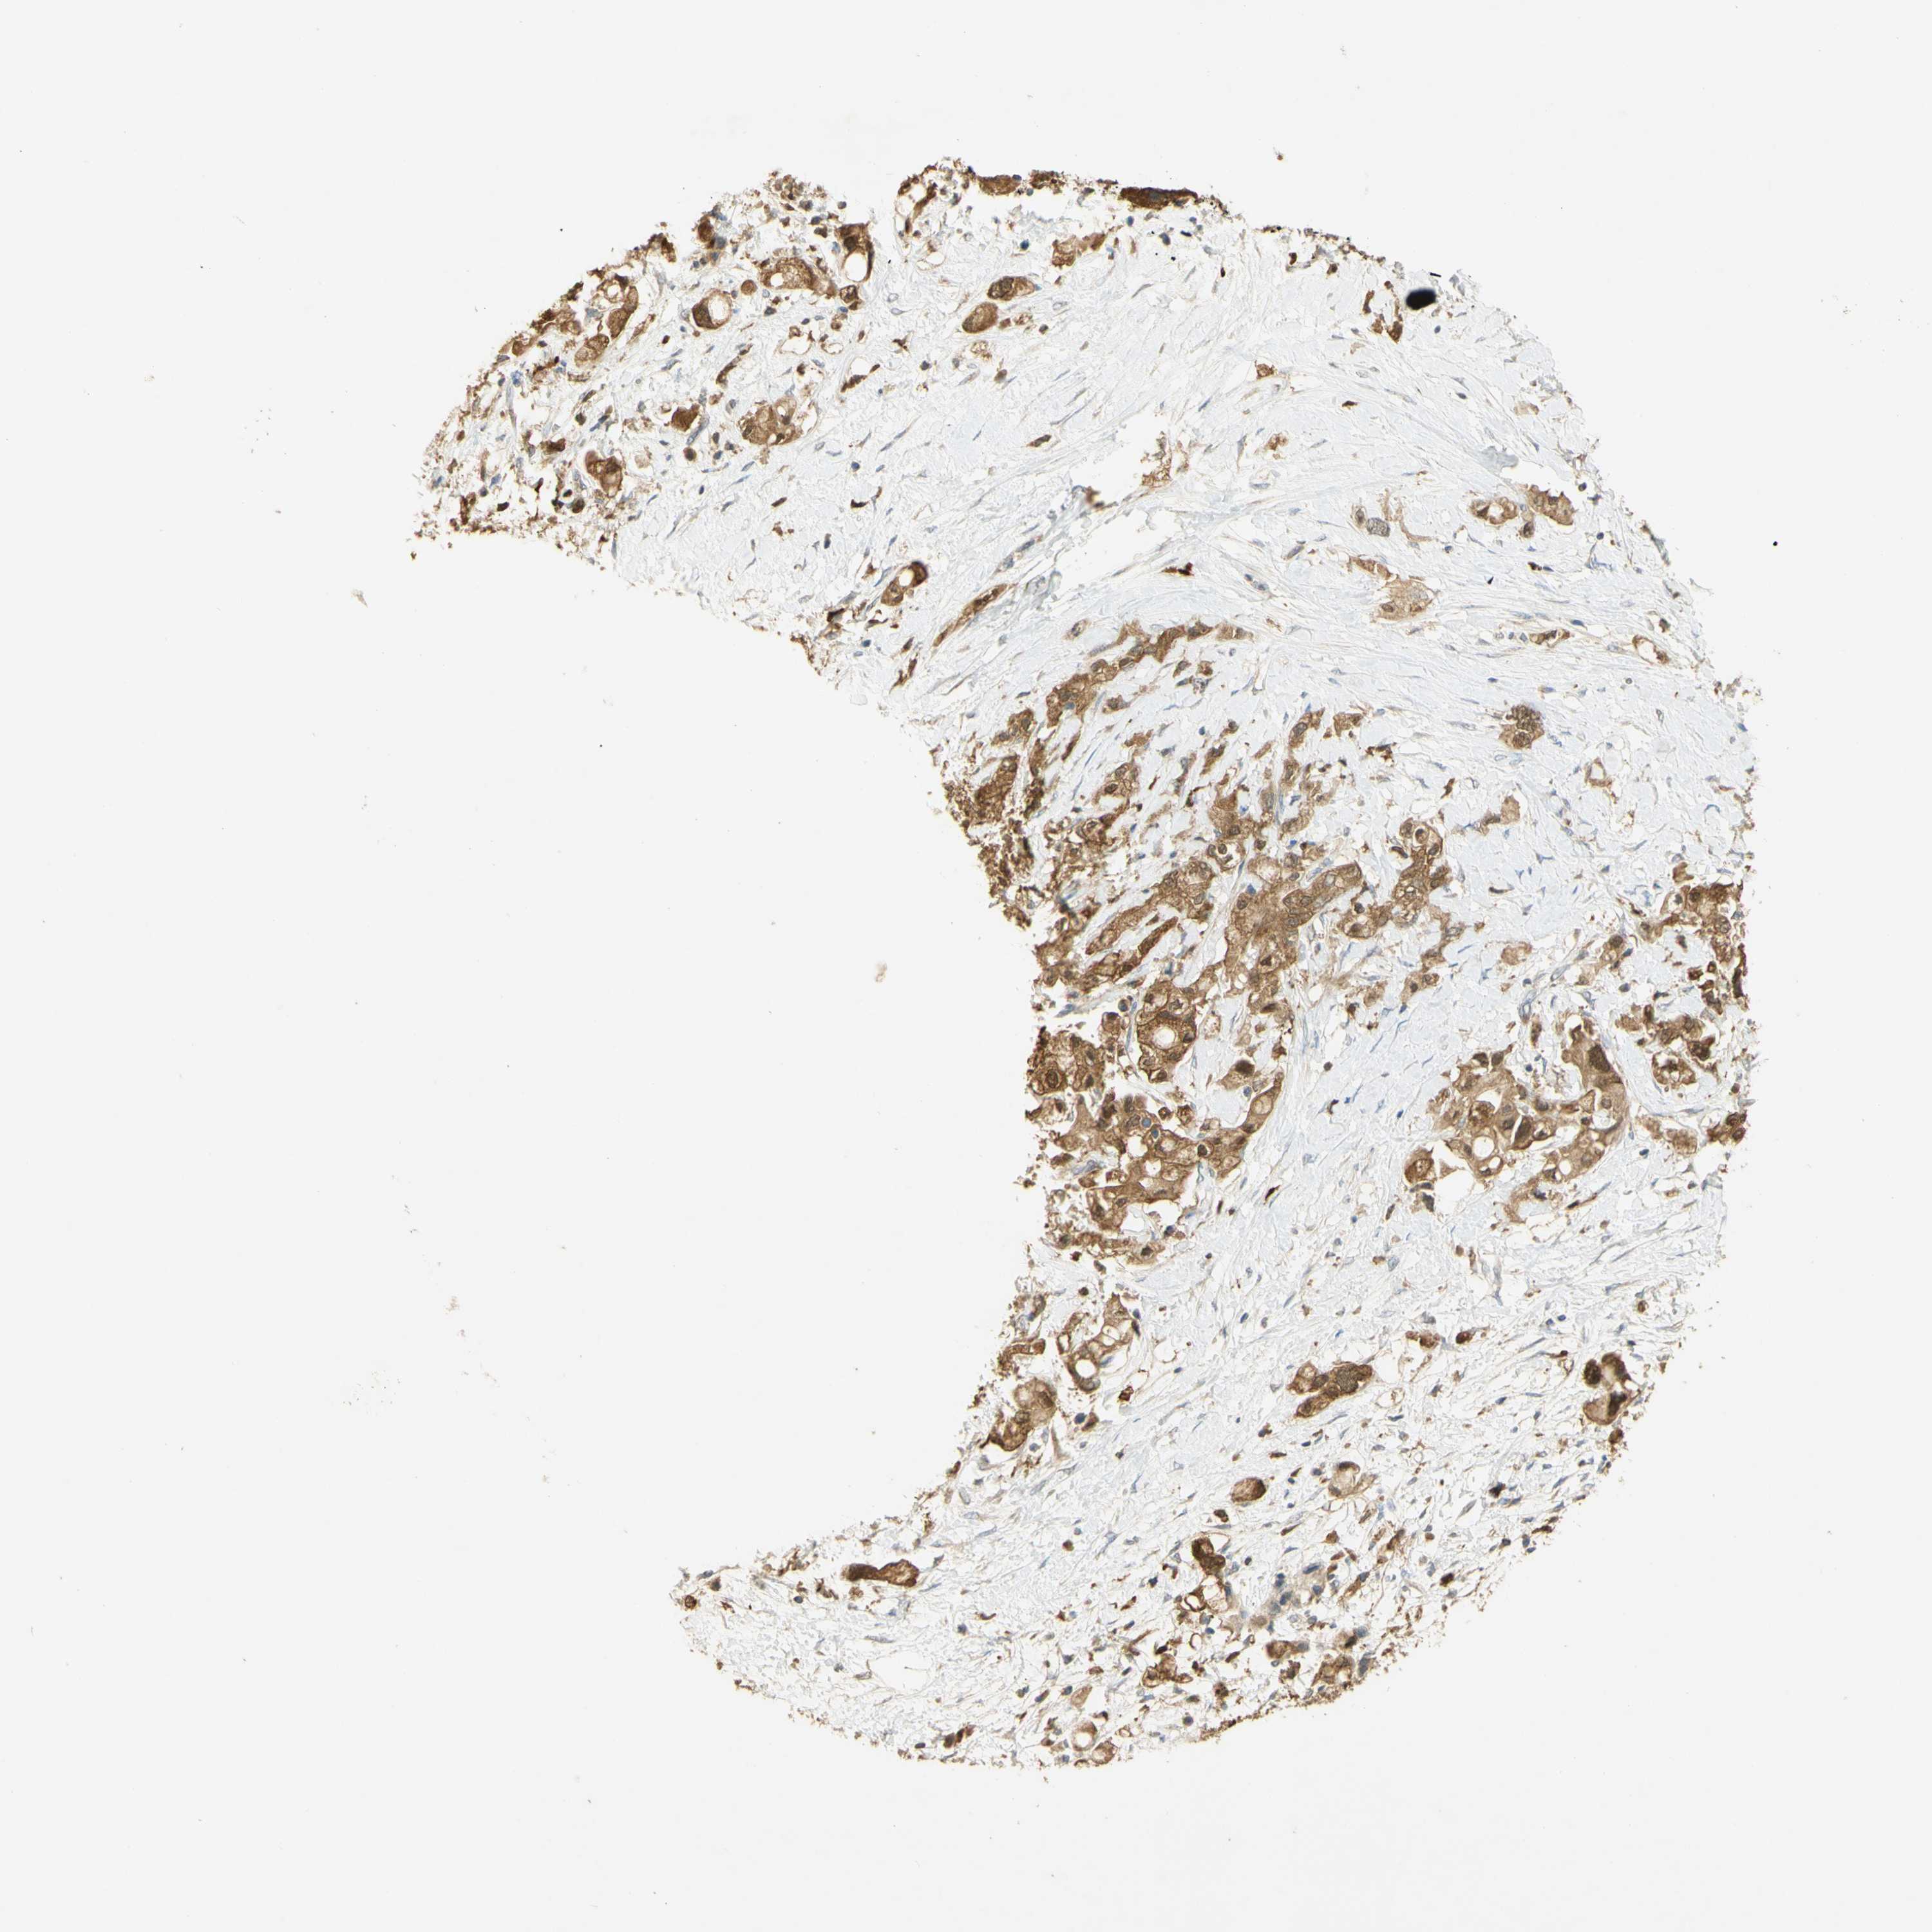

PANCREATIC CANCER - Protein expressioni

A mouse-over function shows sample information and annotation data. Click on an image to view it in a full screen mode. Samples can be filtered based on level of antibody staining by selecting one or several of the following categories: high, medium, low and not detected. The assay and annotation is described here.

Note that samples used for immunohistochemistry by the Human Protein Atlas do not correspond to samples in the TCGA dataset.

Antibody stainingi

Antibody staining in the annotated cell types in the current human tissue is reported as not detected, low, medium, or high, based on conventional immunohistochemistry profiling in selected tissues. This score is based on the combination of the staining intensity and fraction of stained cells.

Each image is clickable and will lead to virtual microscopy that enables deeper exploration of all samples and also displays staining intensity scores, fraction scores and subcellular localization as well as patient and tissue information for each sample.

Antibody HPA003565

Antibody CAB005312

Staining

High

Medium

Low

Not detected

Intensity

Strong

Moderate

Weak

Negative

Quantity

>75%

75%-25%

<25%

None

Location

Nuclear

Cytoplasmic/membranous

Cytoplasmic/membranous,nuclear

Adenocarcinoma, NOS

Adenocarcinoma, metastatic, NOS